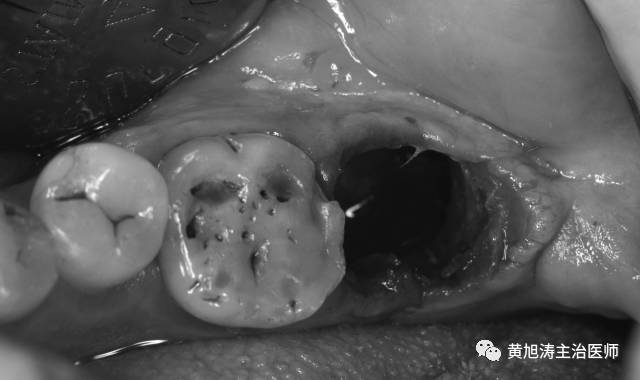

因为当我们拔完牙后,就露出了一个窝洞,然后会慢慢的长肉,大概半个月的时间就可以长好了,但是洞里的骨头生长却是很缓慢,大约要3个月的时间才能完全长好(不要问我为什么,是大学课本写的)。

如果骨头没有长好就去镶牙,由于骨头会慢慢的吸收,拔牙伤口还在变化,假牙与牙龈就会出现间隙,造成食物嵌塞、口臭、假牙松动等一系列问题,就需要把假牙拆掉重新镶了。